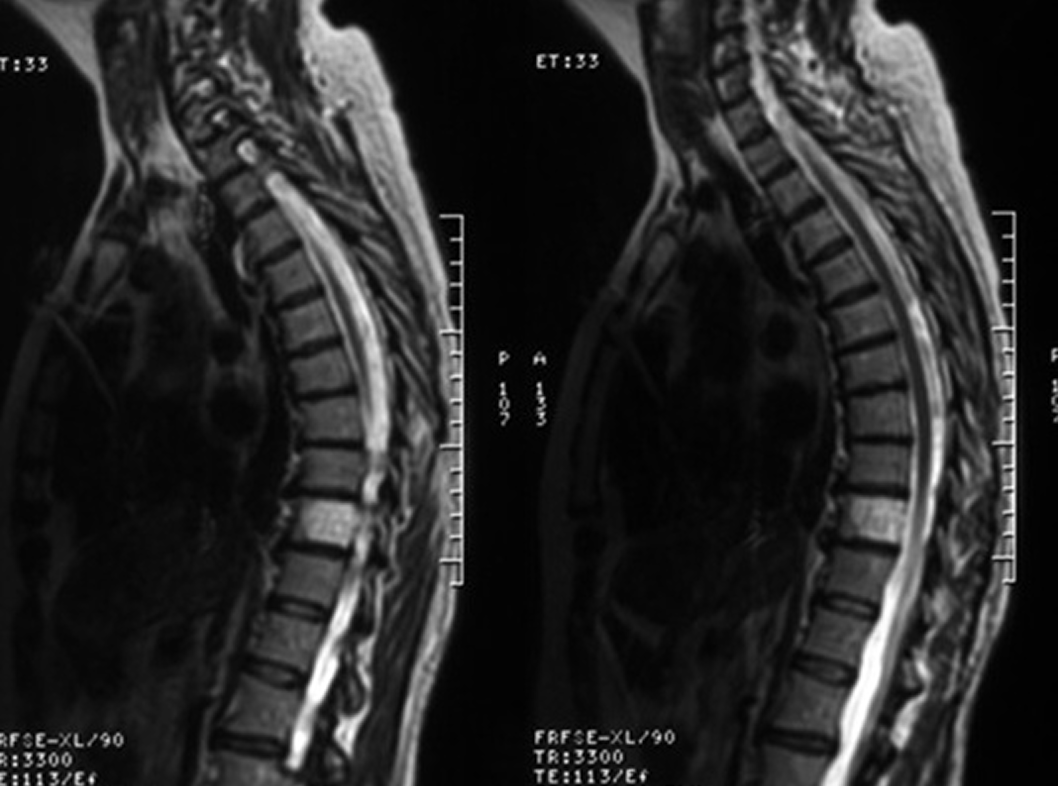

МРТ (магнитно-резонансная томография):

это метод образования изображения, который использует магнитные поля и радиоволны для создания детальных изображений органов и тканей. МРТ может быть полезным для более подробной визуализации гемангиомы и ее окружающих тканей.